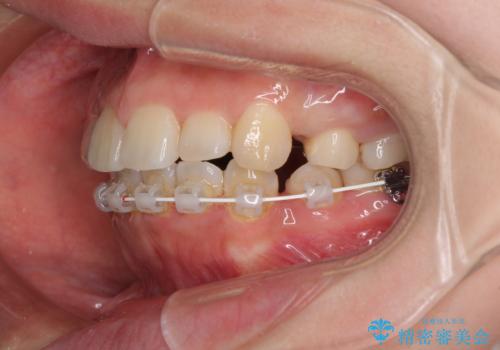

デコボコと膨らんだ口元 ハーフリンガルによる抜歯矯正とインプラント補綴治療

- ハーフリンガル

目立たない装置を希望されたので、上顎が裏側装置のハーフリンガルを選択し、上下左右の小臼歯(計4歯)を抜歯して矯正治療を行うこととしました。

また、左下の奥歯は抜歯が必要な歯であったため、矯正治療中の良いタイミングで抜歯とインプラント埋入を行い、矯正治療後にオールセラミッククラウンで補綴治療を行うこととしました。

デコボコの解消までは非常にスムーズでしたが、咬合力が強いためか、スペースを閉じるまでに長い期間を要しました。

矯正治療途中にインプラント埋入と仮歯の装着を行ったことで、しっかりとした奥歯の咬み合わせで終了させることができました。